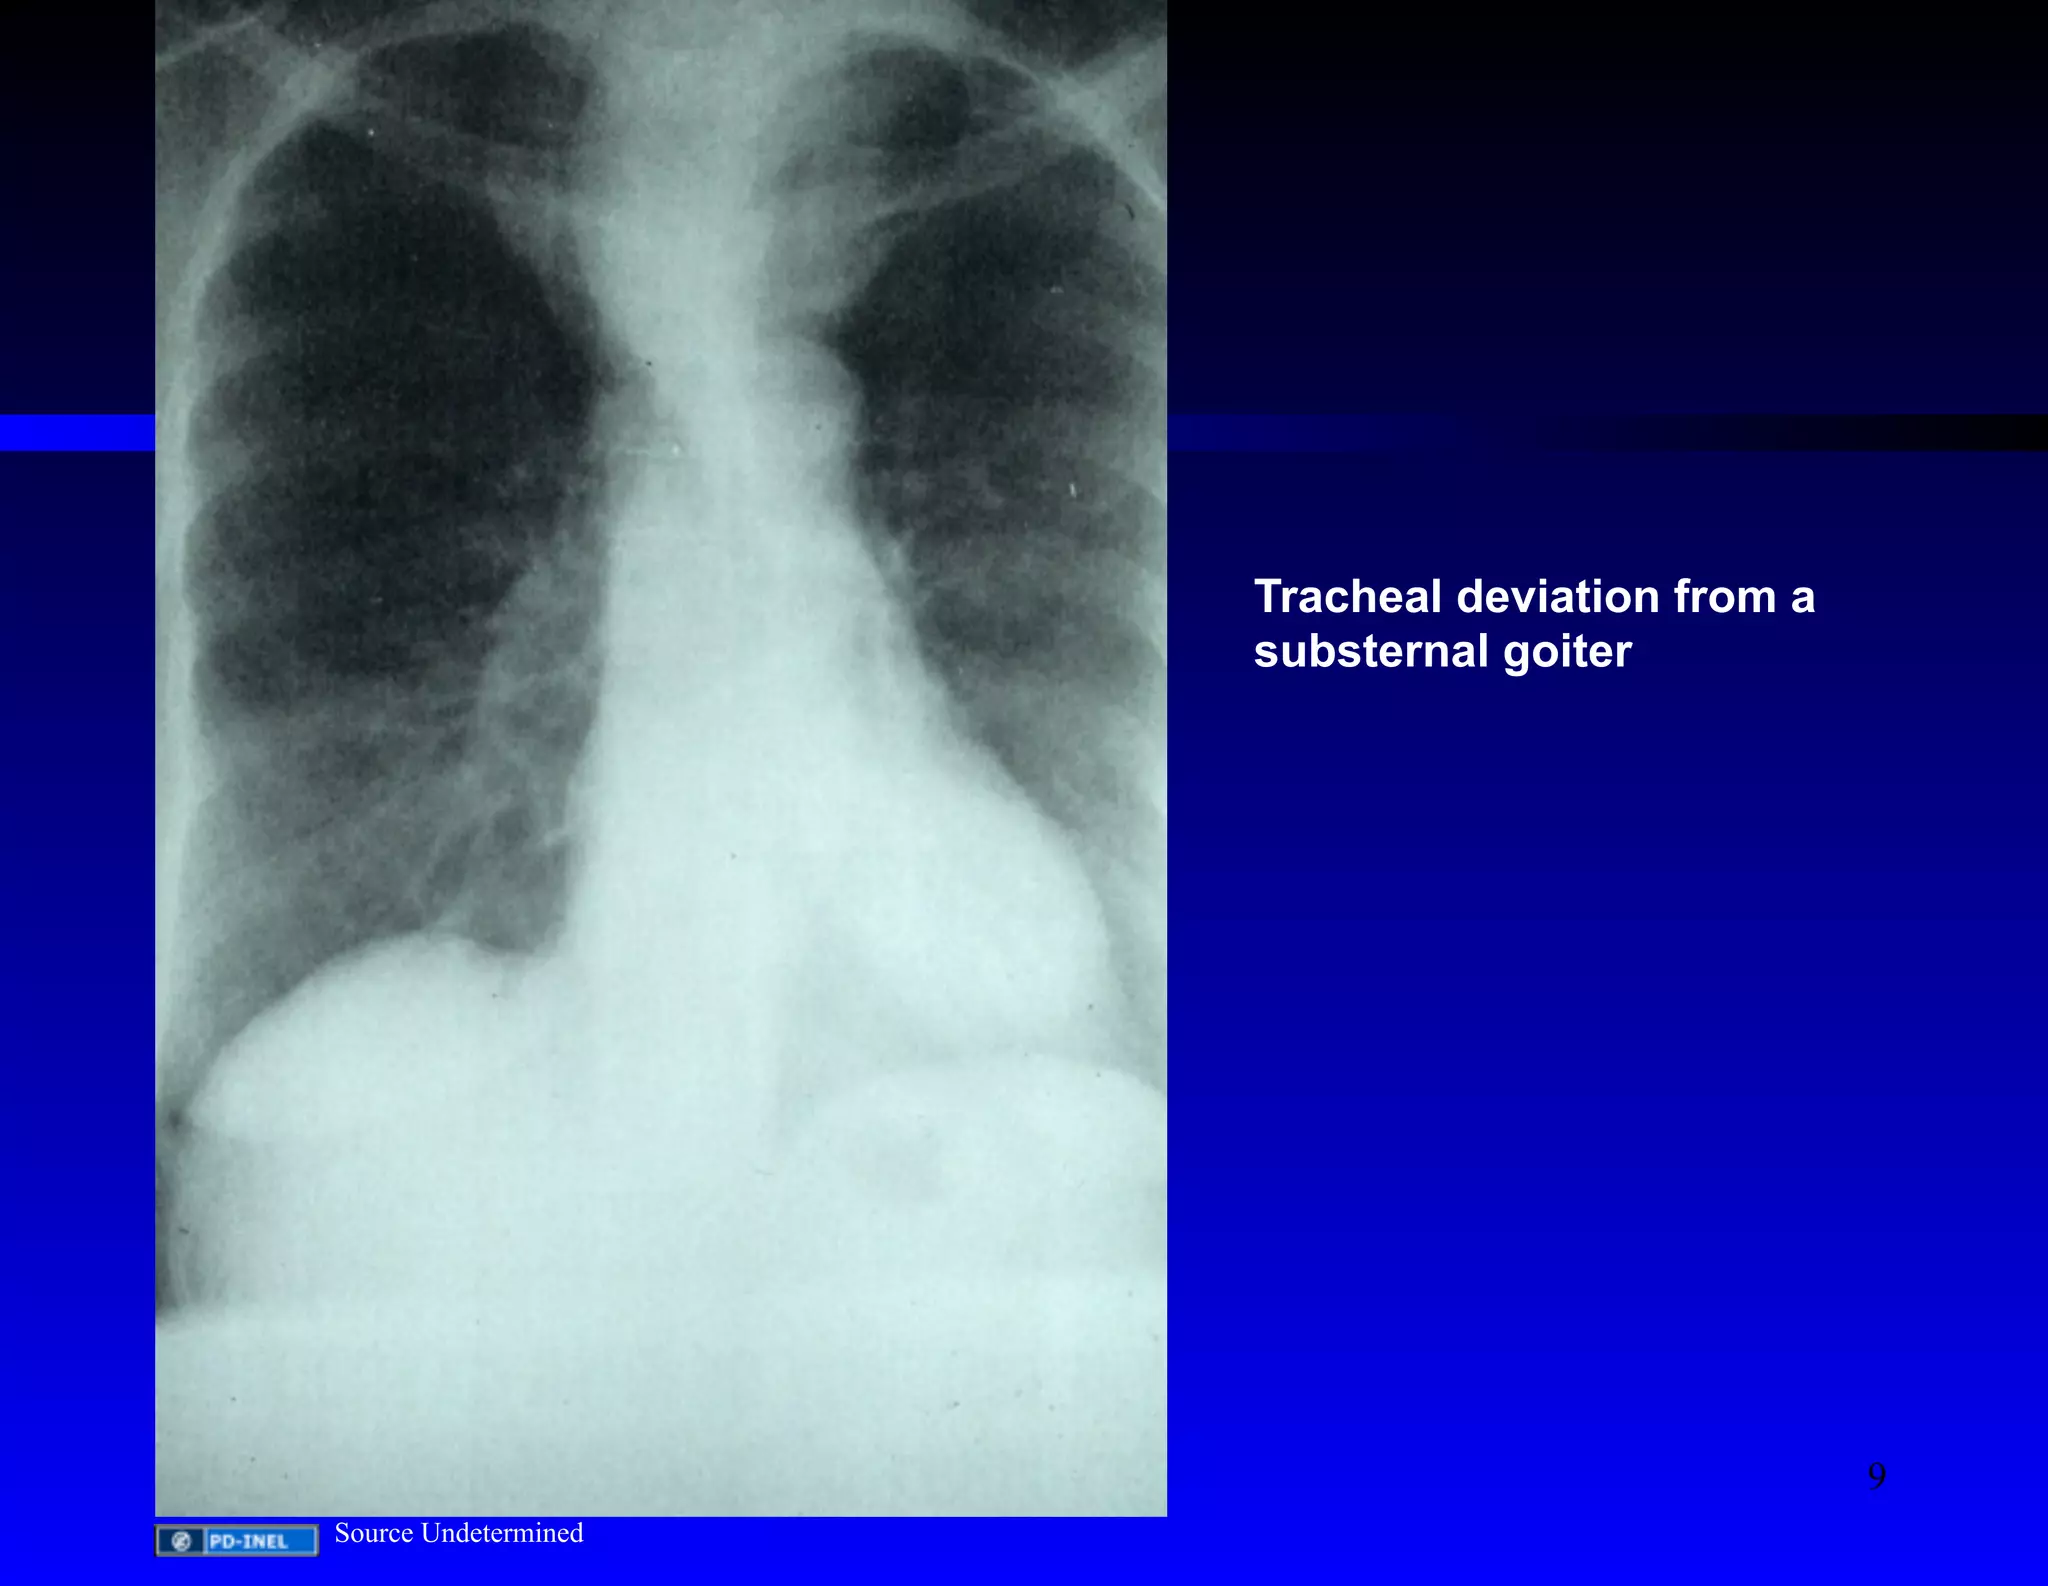

Tracheal deviation from a

substernal goiter

Source Undetermined